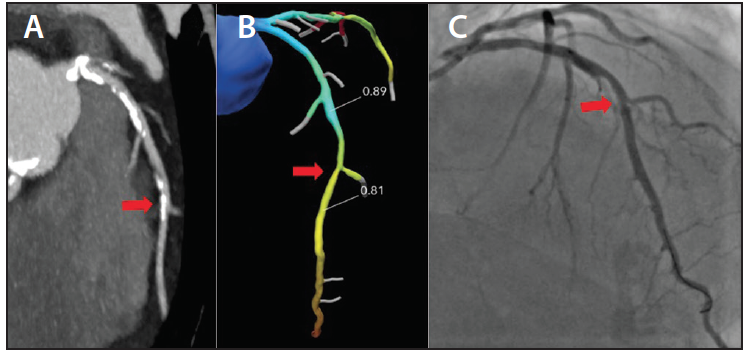

Fractional flow reserve derived from CT (FFRCT) has rapidly progressed and is being used clinically in Europe, Canada, Japan, and the United States. FFRCT is based on standard CCTA imaging and utilizes heart rate control with β-blockers and sublingual nitroglycerin to achieve hyperemia. FFRCT is more accurate than CCTA for identifying narrowing in heavily calcified coronary arteries.6 FFRCT may be particularly useful to adjudicate intermediate stenosis found on CCTA. The method developed by HeartFlow, Inc. is currently the only FDA- and CE Mark–cleared FFRCT technology. In short, a three-dimensional (3D) anatomic model of the epicardial coronary arteries, aorta, and myocardium is created. Machine learning techniques aid in creating a mesh of the coronary lumen with subvoxel accuracy.7 These same machine learning techniques allow for interpretation of the lumen for 3D anatomic modeling in calcified vessels that is superior to that of the human eye. For each vessel supplying the myocardium, resting and hyperemic microvascular resistance are quantified by the 3D anatomic and microvascular resistance models. Using computational fluid dynamics, a color-coded, 3D anatomic model with FFRCT values available in every location of the coronary tree is generated. A simple point-and-click tool can then be used to display FFRCT values in the desired location. When the FFRCT value is combined with the patient-specific anatomic coronary map, functionally significant lesions can be identified (Figure 1).

Figure 1. FFRCT of an intermediate lesion in a symptomatic patient with multivessel disease. Panel A shows a maximum intensity projection of the left anterior descending (LAD) coronary artery on CCTA, where a mid LAD lesion (red arrow in all panels) was read as intermediate severity, with 50% to 70% stenosis. Panel B shows FFRCT analysis with a value of 0.81 beyond the lesion. On invasive angiography for PCI of a severe left circumflex lesion, the FFRinv value was 0.85, supporting the decision-making from the FFRCT study (C).

Courtesy of Elvis Cami, MD.